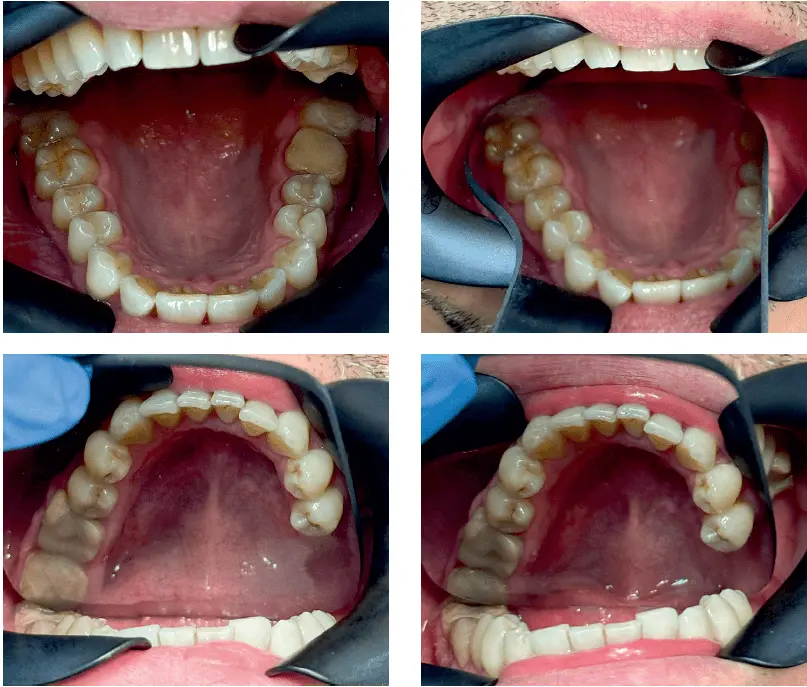

Artykuł opisuje rekonstrukcję implantoprotetyczną braku skrzydłowego lewostronnego w żuchwie oraz odbudowę braków jakościowych w szczęce oraz żuchwie wkładami koronowo-korzeniowymi oraz koronami i nakładami porcelanowymi.

Na podstawie badania klinicznego oraz badań obrazowych stwierdzono znaczne zniszczenie twardych tkanek zębów oraz zmiany w okolicy okołowierzchołkowej zębów 36, 37, zajęcie furkacji zęba 37 oraz obecność zatrzymanego zęba 38.

Po konsultacji z chirurgiem stomatologicznym stwierdzono, że zęby 36, 37 nie nadają się do odbudowy protetycznej. Zęby 36, 37 zakwalifikowano do ekstrakcji z natychmiastową reg...